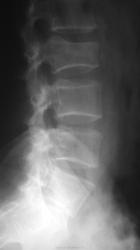

От крестца, особенно на боковой, сомнительный огрызок...

Вот симбиоз Л5 с крестцом мне не понятен, плохо проработана боковая, косвенно похоже на антелистез, но "зуб" не дам...

Еще как при делах.

Еще как при делах. Именно неясность  с L5/S1 наводит на мысль об аномалии/варианте развития.